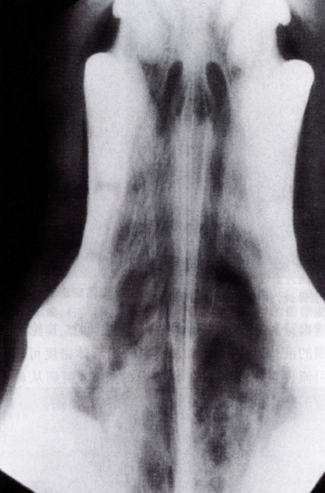

鼻曲霉菌病的X线征象为鼻腔内界限清晰的病变区域以及前端的射线可透性增加。具有代表性的是尽管犁骨表面有凹凸不平的表现,但犁骨和面骨并未受到损害。在极少数的重病情况下,可能会出现这两部分和筛板的破坏。X线片上还可能出现不透明的液性高密度阴影。额窦内的液性阴影主要是该部位的感染或者排除受阻而引起的粘液蓄积造成的。在一些动物仅表现额窦感染。尾部的,通过x光照片可以在筛鼻甲骨部分发现一混合物,这主要是断掉的鼻甲骨,吞咽的粘液,分泌物和真菌斑块的混合物。在一些特殊情况下,会出现肉芽中或者真菌球。

图2:x光片显示双侧鼻腔均存在明显的局部鼻甲溶解,犁骨尚算完整